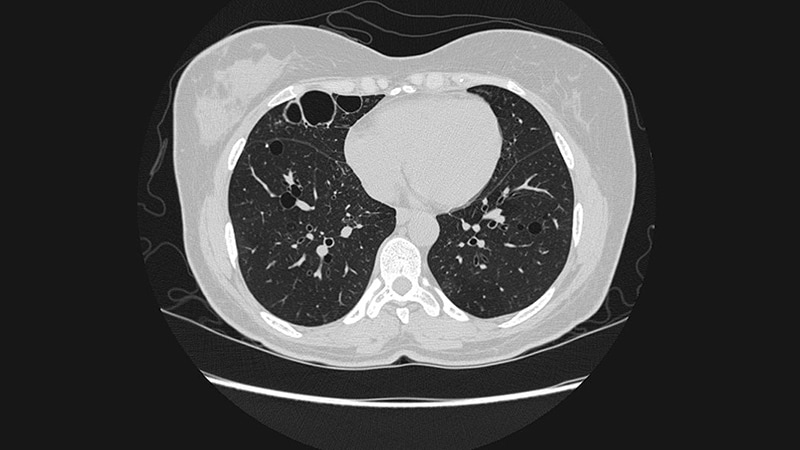

• CHEST 2023 Dietary Changes to Microbiome May Improve Lung Function A study of firefighters who worked at the World Trade Center in New York in the aftermath of the 9/11 attacks suggests that a low-cal Mediterranean diet may protect against lung dysfunction.